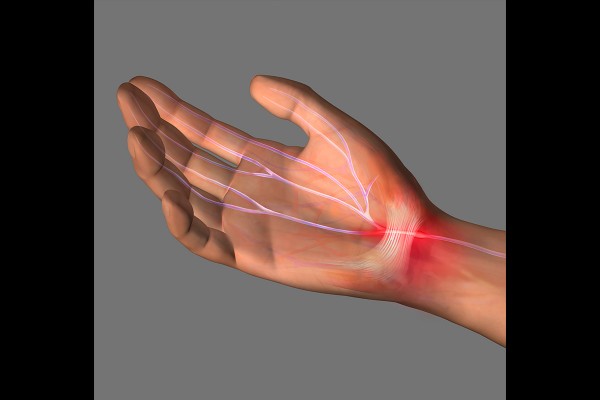

오늘은 대표적인 손목 통증 및 손 저림 질환, 손목터널증후군 내시경 수술사례를 통해 수술법과 재활기간에 대해서 알아보겠습니다.

시간이 지나면 자연스럽게 좌/우로 나눠진 횡수근인대가 연결되며 손목터널이 넓어지는 효과를 얻게 됩니다.